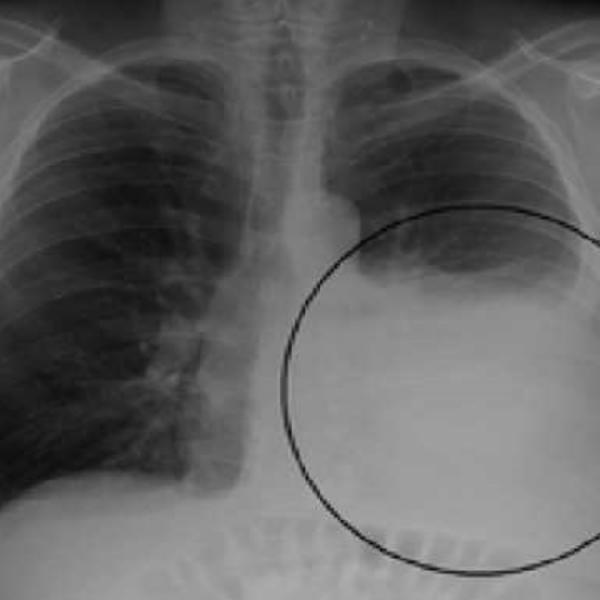

Karcinom (rak) pluća je zloćudni tumor koji najčešće nastaje usled promena ćelija sluznice bronha (glavni disajni put), pa ga još nazivamo i karcinom bronha.

Ne može se preneti sa čoveкa na čoveкa, zato što nije zarazna bolest. Rak pluća jedna je od najčešćih malignih bolesti u svetu i u Srbiji i ujedno je najčešći uzrok smrti od raka kod oba pola. U Srbiji od ovog tipa raka, prema najnovijim podacima IZJZ „Dr Milan Jovanović-Batut”, svake godine oboli 6.000 ljudi, a umre oko 4.600 ljudi.